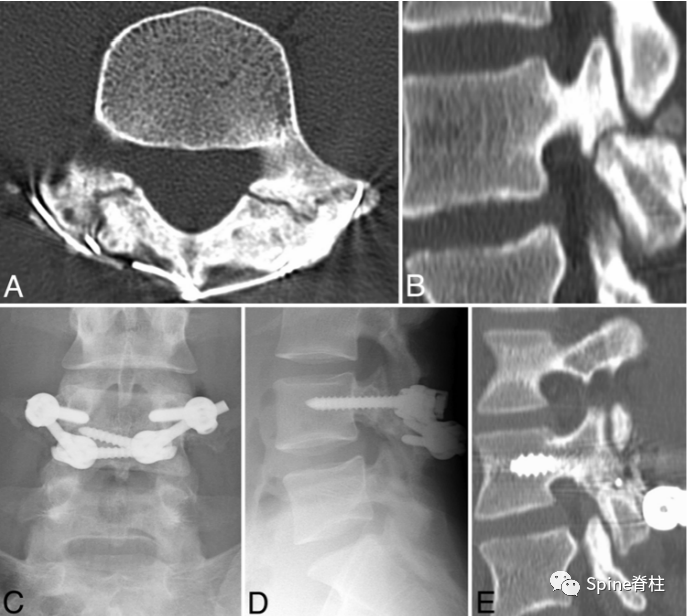

峡部裂的CT分型:A=早期(线性骨折),B=进展期(明显的骨间隙),C=终末期(假关节形成)

右侧为进展期峡部裂,左侧为早期峡部裂,右侧图片是支具固定7个月后愈合

图:腰5双侧峡部裂,右侧为最早期,左侧为晚早期